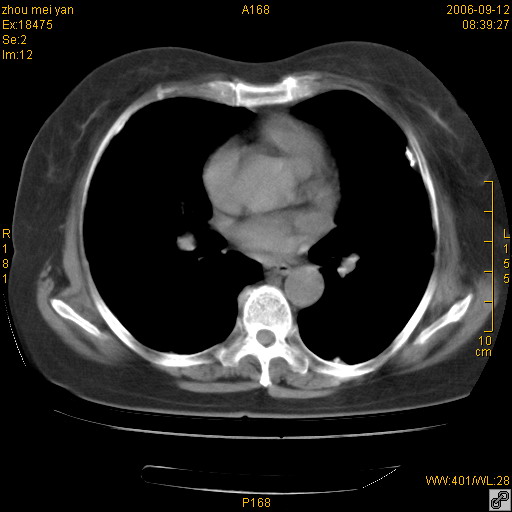

患者、女、55岁。因心率失常住院检查ct发现胸部多发结节。腹部b超肝、胆、胰、脾、肾、子宫附件未见异常。无结核病史,无粉尘接触史。请大家来会诊。谢谢!

双侧胸膜多发结节,形态不规则,边缘较清楚,每一个结节中心似乎都有钙化点的特征,与胸膜广基相切。临床无结核病史,无粉尘接触史。

胸膜间皮瘤可能性大。在气管隆突前可见一肿大淋巴结影。

影像表现十分有特点:双侧肋胸膜及膈胸膜广泛散在分布大小在2至6mm左右,较大病灶中心可见钙化。

病变位于胸膜,多发结节,边界清楚,内见小结节状钙化。其它未见异常。

考虑恶性胸膜间皮瘤可能性大,病灶位于胸膜,以宽基地与胸膜相连,呈结节样改变,部分病灶内可见点状钙化影。请各位老师多多指导!

双侧肋胸膜及膈胸膜广泛散在分布大小不等结节影,较大病灶中心可见钙化。